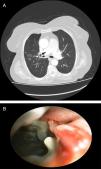

A 83-year-old female patient presented to our clinic with complaints of chronic dry cough, weakness and anorexia. On her physical examination, inspiratory crackles were present on right upper-lung field. Postero-anterior chest X-ray revealed infiltration on right middle zone. Her symptoms were not improved after antibiotic treatment. Acid fast staining (AFS) was negative for three sputum samples. Thorax computed tomography revealed tree-in-bud appearance on anterior segment of the right upper lobe (Fig. 1A). We performed fiberoptic bronchoscopy. On the right secondary carina (RC1), bronchonodal fistula was viewed. Additionally, anterior segment of the right upper lobe was obliterated (Fig. 1B and Video). Bronchial washing from right upper lobe and forceps biopsies from bronchonodal fistula were obtained. Biopsies revealed entirely necrosis. AFS of bronchial washing revealed positive. Patient was negative for human immunodeficiency virus infection and other major immunosuppression state. Patient were underwent anti-tuberculosis treatment for 6 months. At the end of the treatment, her symptoms and radiological findings were improved.

Lymph node in children or immunodeficient patients diagnosed with tuberculosis can erode adjacent bronchial walls which is called “bronchonodal fistula” and other organs including mediastinal vasculature and esophagus via inflammation and necrosis.1,2 Bronchonodal fistula due to tuberculosis in adult immunocompotent patients are extremely rare.1 During fiberoptic bronchoscopy procedure, bronchoscopists should kept tuberculosis related bronchonodal fistula in their mind if they saw erosion on the bronchial wall especially on secondary carina levels on both side.